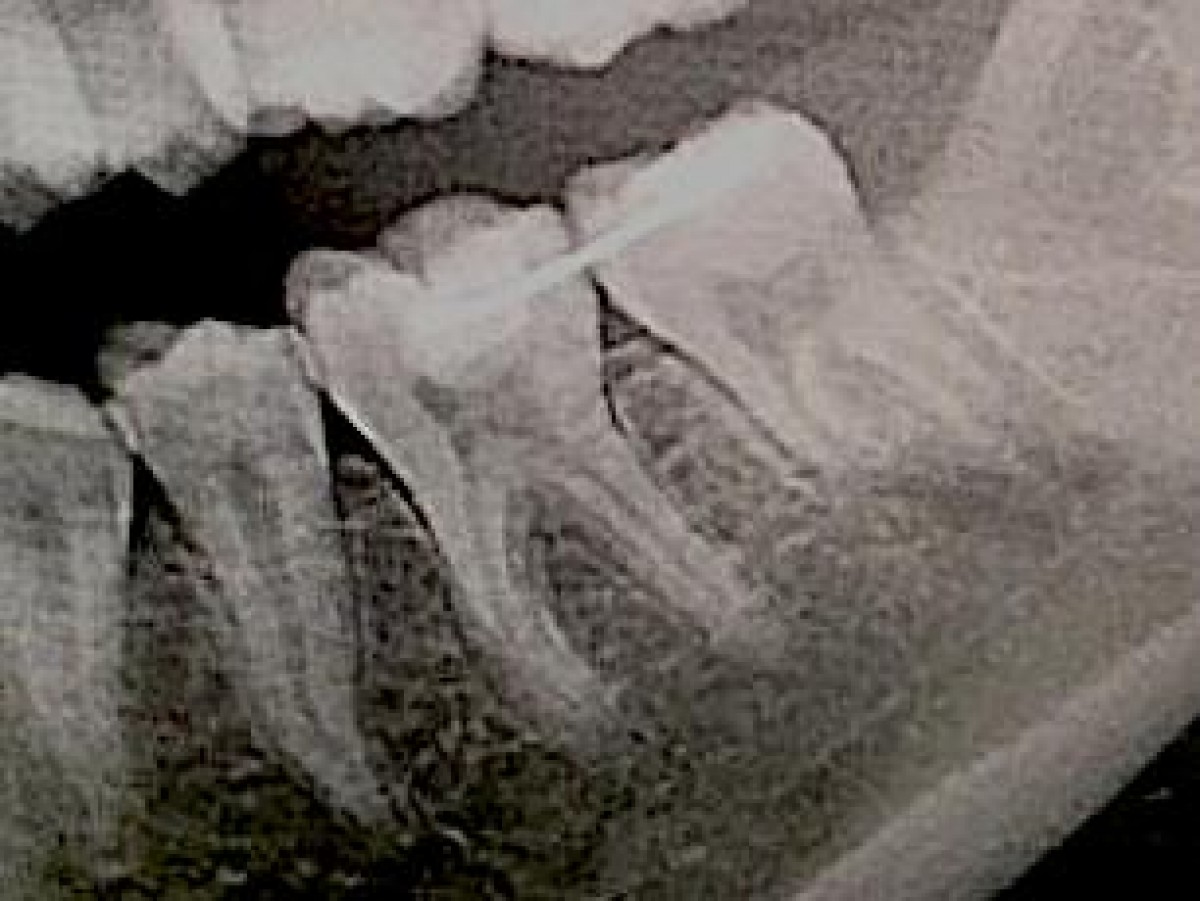

A 27-year-old woman underwent a visit in the Department of Endodontics at Tokyo Dental College Chiba Hospital for conservative treatment of the mandibular left second molar. Intraoral radiography and CBCT images showed a C-shaped root canal in the mesial root and resorption of the distal root due to impact of the crown of the horizontally impacted third molar. Extraction was therefore planned and the possibility of transplanting tooth 38 to replace 37 was considered. Multiple 3D models of these teeth were subsequently prepared based on computer-aided design (CAD) data obtained from CBCT images using a desktop 3D printer. The procedure was explained to the patient using the 3D models and surgical simulation. Finally the surgery was carried out. For temporary fixation to the adjacent tooth, adhesive resin was used.

Postoperative at 2 months showed no vitality of the transplanted tooth, so an endodonthic treatmet was performed. At one year of follow up, any anomaly was found and the patient was able to chew with the transplanted tooth and radiographs indicated a successful postoperative clinical course.